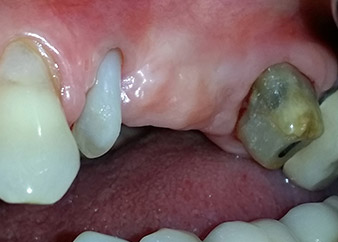

A 58-year-old female patient complained of pain and increased mobility of her bridge abutment tooth 24. Periodontal inflammation was present with pocket depths of 7 mm mesiobuccally and more than 12 mm distally, as well as third-degree furcation involvement. Moreover, the radiograph revealed an extensive periodontal lesion around the apical region of the (alio loco) endodontically pretreated tooth 24 (Fig. 1).

One year earlier, teeth 25 and 26 had been extracted due to trauma and for endo-perio reasons, prior to the placement of the bridge. A combined endo-perio lesion was diagnosed for tooth 24, of unclear aetiology. The patient wanted to keep her bridge abutment teeth 24 and 27 and would not accept a final, or even temporary, removable prosthesis. Therefore, it was agreed to make all efforts to retain both teeth, in spite of their poor prognosis as based on radiological and clinical findings.

Placement of two submerged implants was planned at sites 25 and 26, in a surgical session with open periodontal debridement and apicoectomy of tooth 24. Due to the vertical bone deficiency at the future implant site, an internal sinus augmentation was also planned.